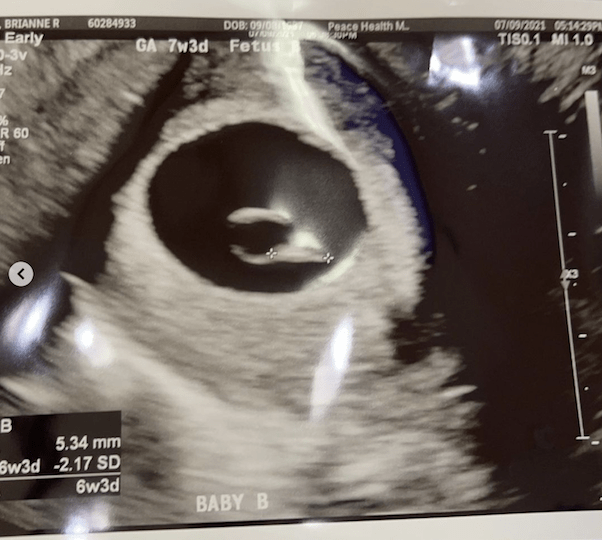

However, that joy — which came at the “7 week and 6 day” mark, was tempered with caution. “Baby B was measuring smaller then baby A,” Brianne explained, “so much so they couldn’t get a heart beat count. The tech that read my results thinks baby B is no longer viable because of that.” (The photo above is the sonogram of Baby B that Brianne shared.)

In a post several days later, Brianne confirmed that “Baby B” was, in fact, no longer viable.

“Baby B didn’t have a heart beat,” she wrote. But that didn’t mean Brianne was no longer overjoyed by the prospect of becoming a mom: “Baby A is so perfect!” she went on. “Heart beat was 172!! I’m thinking girl!”